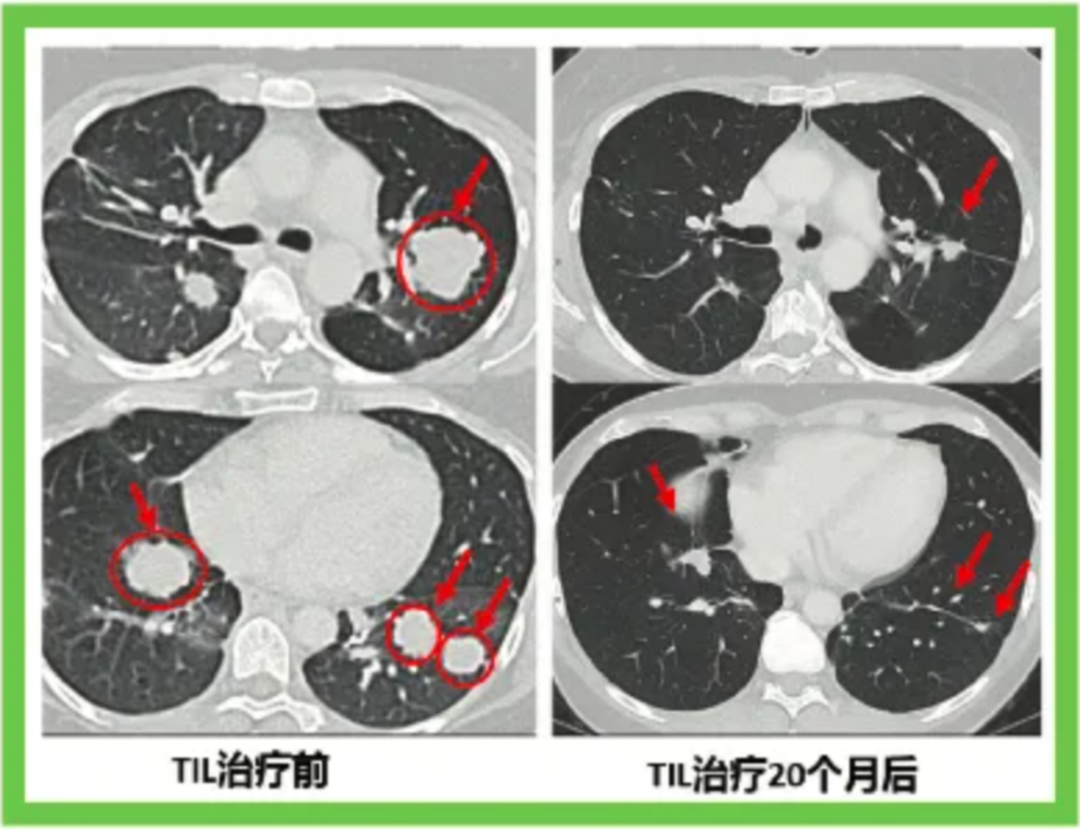

下面的对照图可以非常明显看到治疗前肺部布满的肿瘤,包括一些个头非常大的,第二次TIL治疗20个月后,这些肿瘤都非常显著地缩小了。